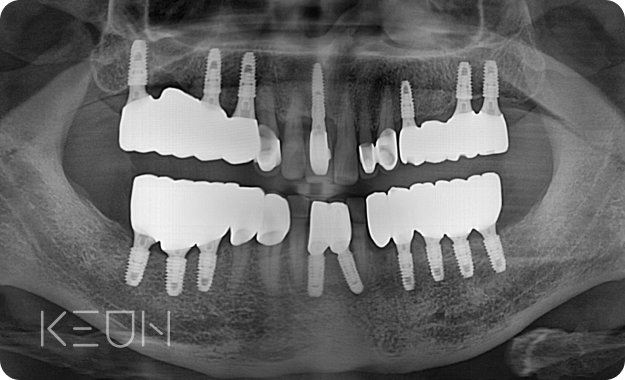

어르신 복합치료 전후사진.

- After

*모든 치료전/후 사진은 환자분의 동의하에 촬영 및 게시되었습니다.